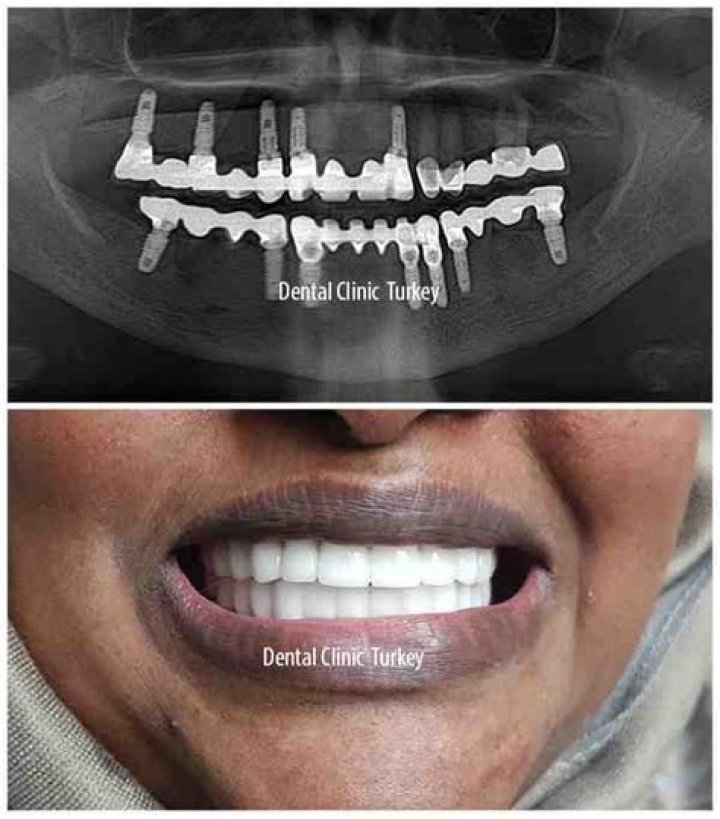

Can I get a full mouth of dental implants?

Dental implants can be used to replace a single tooth or several teeth, or to support partial or full dentures. Implants and crowns remain inside the mouth and do not require any adhesives to hold them in place.

How many implants are needed for full mouth?

In general, implant dentures that are being utilized for full teeth replacement on the upper or lower dental arch require only a few dental implants to successfully and comfortably stabilize the denture. For some patients, two to four dental implants are sufficient. For others, six or more implants may be necessary.